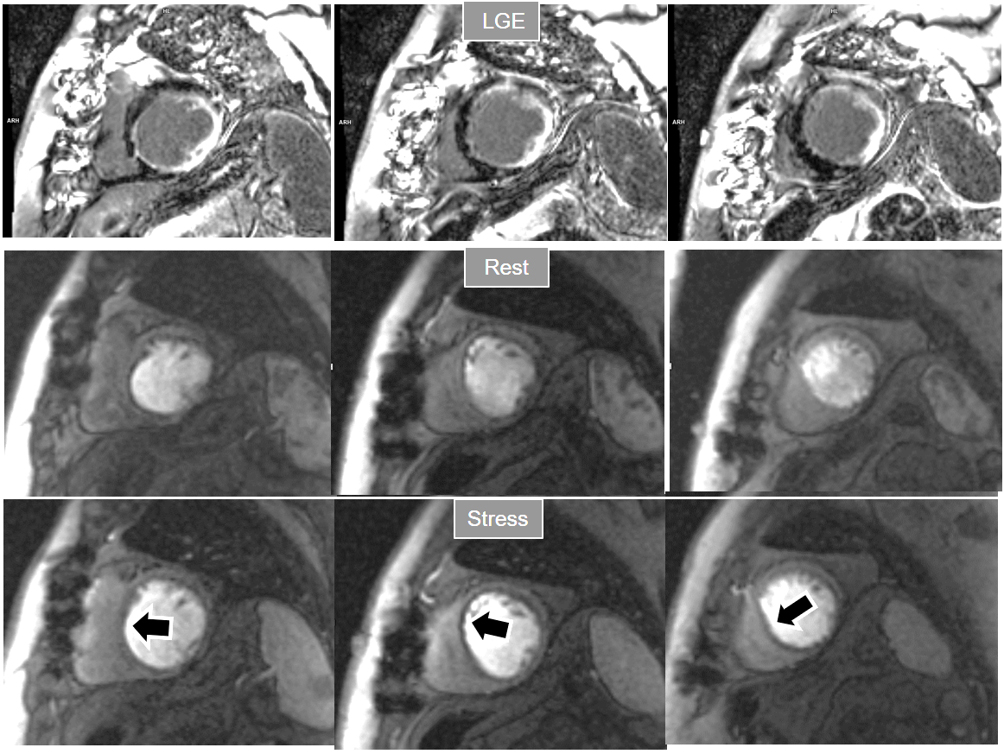

Perfusion defects in different territories can be detected in case of multivessel disease (Fig. 7) and, in patients with severe 3-vessel CAD, the perfusion study may show a global, intense, persistent defect which is readily recognizable (Fig. 8).

Fig. 8.Three-vessel perfusion defect. Stress and rest studies in a patient with severe left main and 3-vessel CAD (arrows, on the right panels) showing an inducible perfusion defect in most, if not all, of the myocardial segments during vasodilatory stress.

A not infrequent finding is a diffuse, annular, transient, subendocardial defect not present at rest (Fig. 9), which, in the absence of any recognizable obstructive lesion in an epicardial coronary artery, has been deemed to correspond to diffuse microvascular dysfunction (MVD) [41, 42]. CMR perfusion is sensitive to both the downstream effects of discrete epicardial stenoses and those due to disturbances of coronary microcirculation, and subendocardial hypoperfusion is on the pathophysiological basis of each one. For this reason, theoretically, a global, inducible subendocardial defect, could also be due to multivessel epicardial disease with balanced ischemia. In practice, however, this latter instance presents with extensive but heterogenous defects in terms of intensity, persistence and transmurality and, not rarely, also with perfusion defects at rest (Fig. 10A). Importantly, an accompanying induced contractile disfunction may be found in particularly impaired regions (Fig. 10B), a finding which is never seen in MVD.

Fig. 10.Multi-vessel perfusion defect. (A) Global stress hypoperfusion in a patient with multivessel CAD. Observe the non-uniformity of the defect, with different degrees of intensity and transmurality and, also, with the presence of a defect at rest (arrow), in the absence of LGE. (B) End-systolic frames from cine studies at the same level of the perfusion slices showing inducible antero-septal hypokinesia during stress (arrows).

When considering both, the variability of rest perfusion in the presence of previous MI, and the rather low sensitivity of partially reversible defects, the interest in knowing the actual extension of fixed defects emerges. An option to address the issue is to invert the order of perfusion studies in patients with previous MI, performing the rest study first. This allows for a reliable delineation of the fixed defect that can be easily subtracted from the inducible one, when present (Fig. 18). Moreover, in the case of patients with advanced, severe CAD, in whom a combination of infarcted regions and underperfused territories can be expected, a basal rest perfusion study followed by the stress one is even more helpful (Fig. 19). Certainly, the presence of CA in an area of MI after the first rest perfusion study may contaminate the SI of the second one, but this does not preclude the detection, or exclusion, of newly induced defects (Fig. 20).

Fig. 18.Rest/Stress perfusion in chronic myocardial infarction. Patient with previous myocardial necrosis involving most of the LV segments, mainly subendocardial in the anterior and septal regions, and transmural in the lateral wall, as shown in the LGE images (upper panel). The rest perfusion study, performed in first place (middle panel), shows a diffuse subendocardial defect, while, at a subsequent stress study (lower panel), a fair increase in transmurality and extension of the antero-septal defect is seen (arrows) indicating peri-infarction ischemia, while the lateral one remains unchanged. Note the lack of interference of the previous dose of CA on the tissue contrast of the stress study.

Fig. 19.Rest/Stress perfusion in chronic myocardial infarction. Upper panel: LGE study showing subendocardial necrosis of the infero-lateral segments (white arrows). Middle panel: rest perfusion study performed in first place showing a defect extending far beyond the limits of the actual MI (black arrows), indicating impaired perfusion at rest of non-infarcted territories (i.e., myocardial hibernation). Lower panel: subsequent stress study showing an increase in extension and transmurality of the inferior defect (large black arrows) and, also, the appearance of and additional induced defect at the anterior wall (small black arrows). Again, the stress study is not interfered by the previous CA administration.